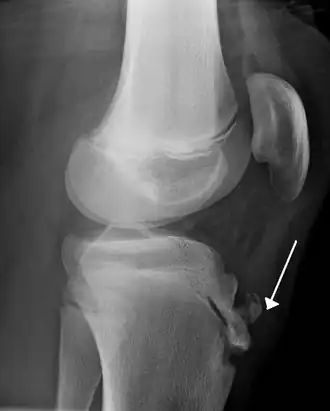

Une radiographie n'est pas nécessaire notamment lorsque le tableau clinique est évocateur et que les douleurs sont bilatérales. Elle peut être utile pour éliminer une autre pathologie si les douleurs sont unilatérales, atypiques ou rebelles au traitement. Initialement on retrouve un soulèvement de la tubérosité tibiale antérieure avec élargissement de son cartilage de croissance ; dans les stades plus évolués, la TTA est fragmentée et on peut voir parfois des calcifications dans le ligament rotulien[2].

IRM d'un Osgood-Schlatter- Radiographie d'un Osgood-Schlatter